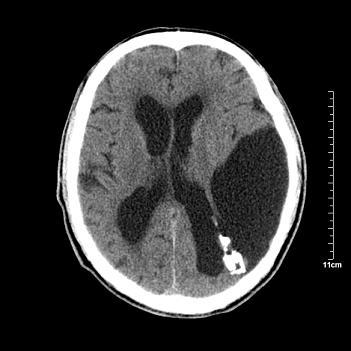

男性患者,72岁,近两天头晕来我院就诊。 因患者血压太高而未做增强,建议病人去市医院做mri检查。等得到mri随访结果再公布给大家。 测及左颞顶枕叶病灶ct值分别为5hu 30hu 729hu。

考虑左侧颞顶枕叶少突胶质细胞瘤。 今天随访患者手术病理结果 病理回报为胶质瘤2级 钙化

左侧颞顶枕叶大片状低密度影,呈均一水样密度,边界清楚,病灶边缘不规则片状钙化,左侧脑室后角扩大,中线结构未见移位,综合来看不像肿瘤,软化灶,钙化不好解释

左侧颞顶枕叶巨大囊性病灶,灶内见小片实性区且灶内及灶周围大量团块状钙化影,灶周水肿少.左侧室枕角内见环形钙化,可见较清晰前壁,钙化与室壁似有间隙.

囊变明显,钙化明显,部分实性组织,轻度占位,左侧脑室受压---考虑 少突胶质细胞瘤,畸胎瘤,寄生虫病

今天追踪患者家属手术病理结果 病理回报为胶质瘤2级并钙化

病理回报为胶质瘤2级并钙化